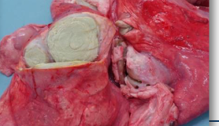

What condition is represented here?

A

Lung abscess

Abscess

How would you differentiate between an abscess, a CLA abscess, and an OPA mass?

• Abscess = smooth and firm

• CLA abscess = irregular and firmer mass with laminated pus

• OPA mass = solid and does not have a capsule

Many people diagnose by incising but it can be done by touch too.